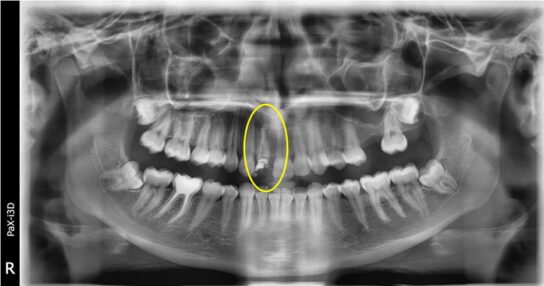

Realizamos radiografía panorámica y periapical de la zona, donde podemos observar que le queda un resto radicular, el cual presenta una gran infección periapical, parece llevar intraconducto un material intraconducto y una obturación provisional sobre el mismo. Esta obturación provisional está completamente suelta y filtrada.

Procedemos a la realización del tratamiento conservador. Empezando por la apicoformación, endodoncia y restauración del diente. A continuación podemos ver una sucesión de radiografías con la evolución del tratamiento del paciente y la intervención realizada.